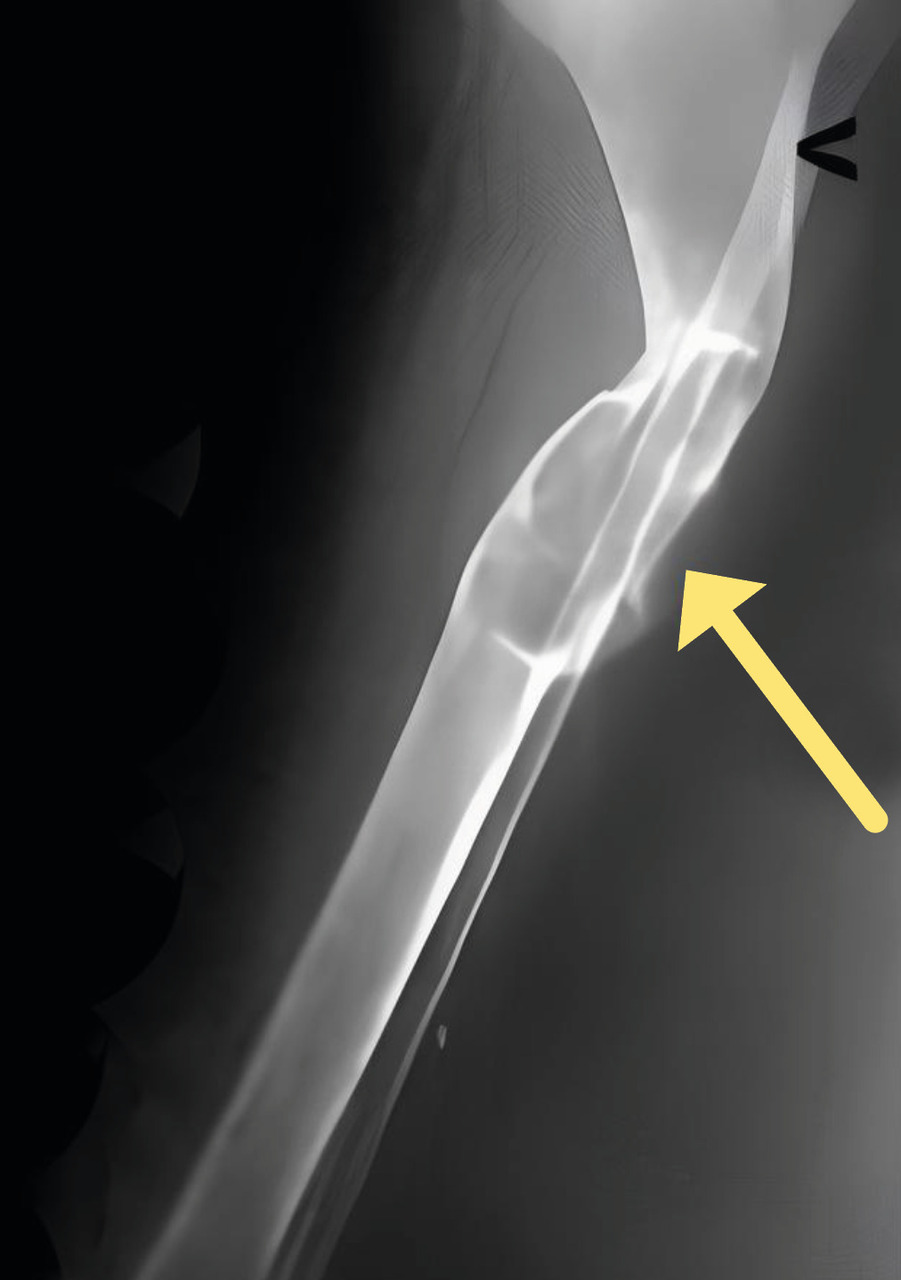

Sur le plan radiologique, une tumeur brune (fig. 2), devenue rare, doit être différenciée principalement d’une métastase osseuse, d’un chondrosarcome ou d’une tumeur à cellules géantes.